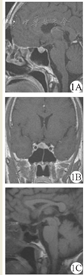

性腺六项检查结果:促卵泡激素(FSH)12.94 U/L↓,黄体生成激素(LH)12.99 U/L,催乳激素(PRL)160.9 U/L,雌二醇(E2)243.2 μmol/L↑,孕酮(P)2.4 nmol/L,睾酮(T)44.99 nmol/L↑。甲状腺功能三项检查结果:游离三碘甲腺原氨酸(FT3)18.05 pmol/L↑,促甲状腺激素(TSH)6.68 mU/L↑,游离甲状腺素(FT4)59.61 pmol/L↑。甲状腺彩超:甲状腺未见异常。入院诊断:垂体腺瘤(垂体促甲状腺激素腺瘤)。术前准备:口服普萘洛尔10 mg,每日3次,5 d后心率降至70次/min。行全身麻醉下经蝶垂体瘤切除术,术前应用地塞米松10 mg,术中经右鼻孔入路,咬除蝶窦前壁1.5 cm × 1.5 cm大小,咬除蝶窦分隔,近右侧咬除鞍底,1.0 cm × 0.8 cm,硬膜电灼后"十"字切开,见有烂鱼肉样瘤组织,质软,血运丰富,彻底刮除,瘤腔内填塞明胶海绵。术后清醒,视力正常,眼球活动正常,瞳孔等大等圆,对光反射灵敏,肢体活动正常,拔除气管插管。当患者被搬离手术床,准备回病房时,突然心率升至167次/min,血压100/60 mmHg(1 mmHg=0.133 kPa),高热,全身皮肤潮红,大汗,考虑甲亢危象。立即给予地塞米松10 mg静脉推注,艾司洛尔降心率,物理降温。迅速静脉滴注注射用甲泼尼龙琥珀酸钠80 mg,1 h后体温降至正常。心率120次/min,艾司洛尔持续静脉泵入。24 h后患者生命体征恢复正常,双手震颤消失。术后第1天复查甲状腺功能:TSH1.17 mU/L,FT3 9.1 pmol/L↑,FT4 74.58 pmol/L↑。术后第2天:TSH 0.856 mU/L,FT3 4.36 pmol/L,FT4 25.98 pmol/L↑。术后第4天皮质醇:21.47 nmol/L↓。注射用甲泼尼龙琥珀酸钠80 mg连用3 d后,改为醋酸泼尼松10 mg口服。术后第6天出院。术后3个月复查颅脑MRI,提示肿瘤无复发。甲状腺功能三项:TSH 0.81 mU/L,FT3 4.1 pmol/L,FT4 15.53 pmol/L,均在正常范围内。影像学检查和病理检查见图1,图2,图3。

注:1A:术前头颅MRI强化(矢状位);1B:术前头颅MRI强化(冠状位);1C:术后3个月复查